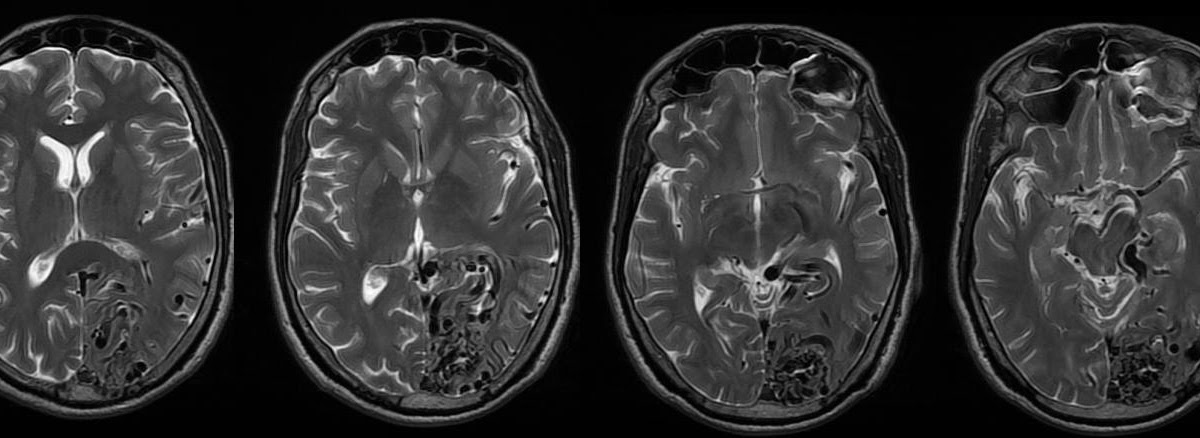

Cerebral diseases

Cerebral diseases 104 фото